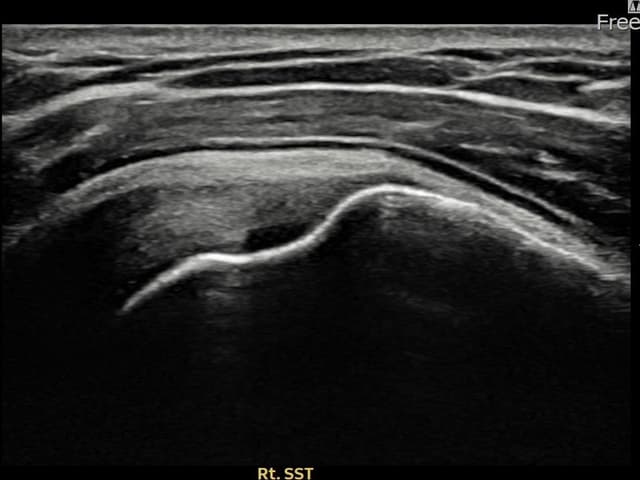

[촬영시기:22.09.06]

[석회분쇄흡입술] 좌측 어깨 통증으로 팔을 옆으로 올리기 어려워진 60대 남성 환자로, X-ray에서 좌측 극상근건 내 석회 침착이 확인되어 석회분쇄흡입술을 시행하였습니다.